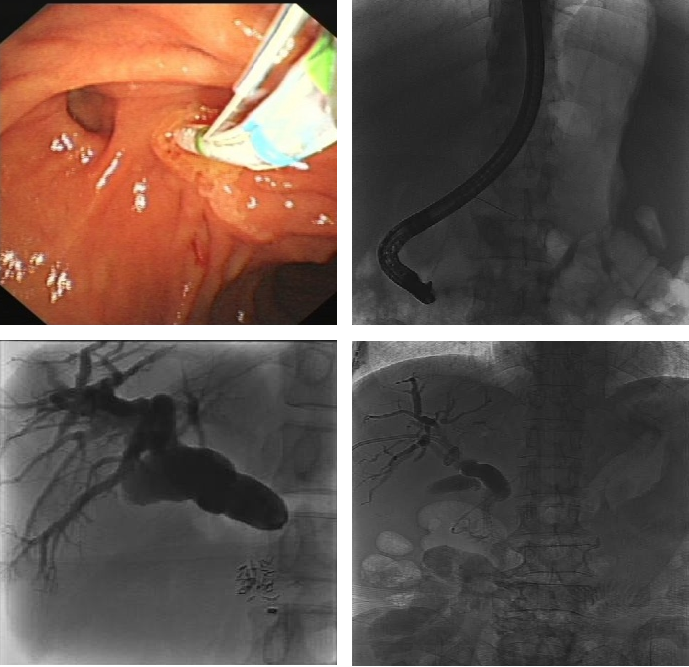

PTCD胆道支架植入术